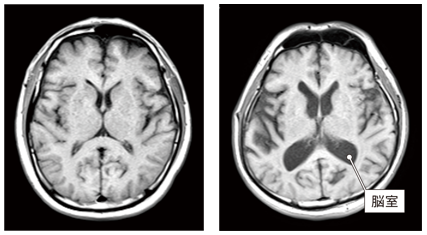

この画像はともに50代の人の脳です。

右の人は脳室(中心にある黒いエリア)が左に比べ拡大しており、脳の萎縮が進んでいると判断されます。

萎縮は脳の機能低下や認知症発症のリスク因子です。

60歳を過ぎても30代並みの若々しい脳を保っている方の例も多くあり、加齢による萎縮の進み方は人によって大きく異なります。